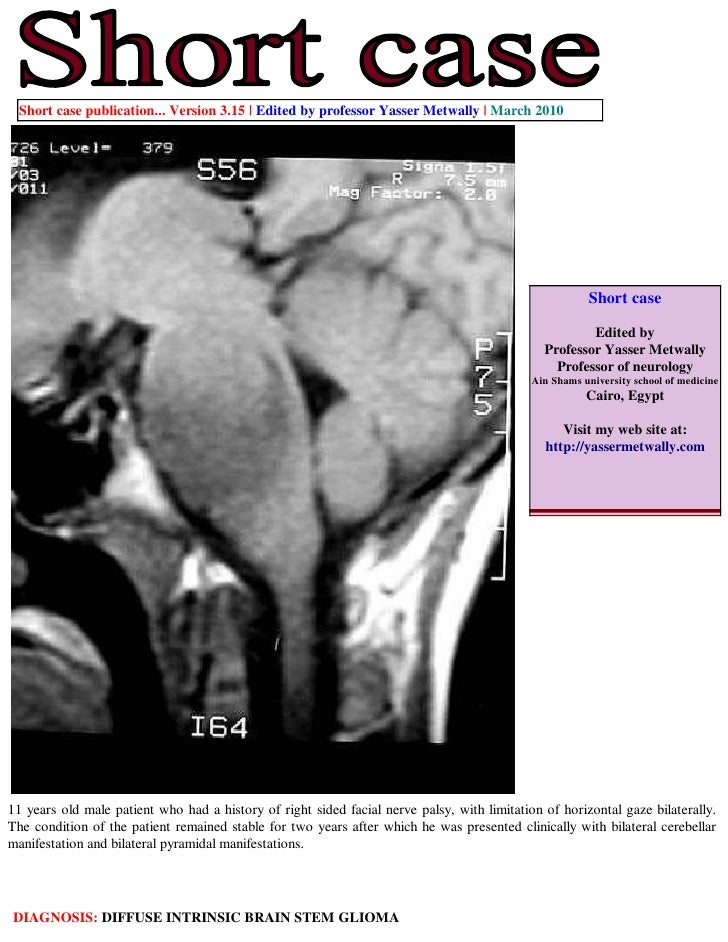

Brain stem gliomas, also called diffuse infiltrating brainstem gliomas, or dipgs, are rare tumors found in the brain stem. Brainstem gliomas consist of a heterogeneous group which vary greatly in histology and prognosis. Gliomas arising in the brainstem (midbrain, pons, and medulla oblongata) account for 10 to 20 percent of all central nervous system focal brainstem glioma.

The brain stem, located deep in the back of the brain, is made up of the midbrain, pons, and medulla.

Diagnosis is a domain of mri, requiring t2, t1 and km. Genes variations tissues related diseases publications pathways drugs. Brainstem gliomas consist of a heterogeneous group which vary greatly in histology and prognosis. 5% cns tumors in adults.